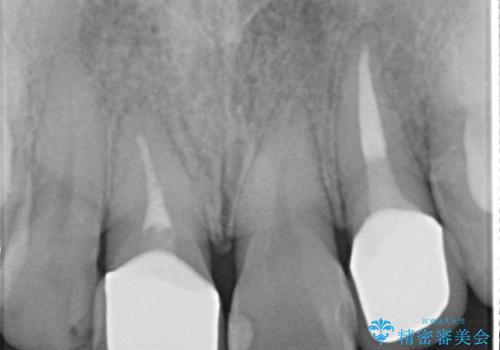

- 患者様は前歯にできものができたということで来院されました。

歯髄診断を行い、失活していると判断して根管治療を行いました。

歯茎の出来もながなくなり、患者様にセラミックの色も満足いただけました。